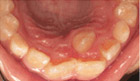

儿童蛀牙

儿童正畸

窝沟封闭